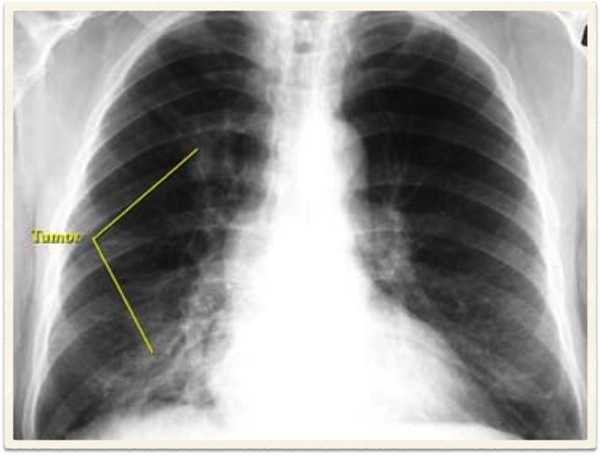

Radiological Report: Cardiac size within normal limits. Both lungs show severe overinflation typical of COPD. No sign of mass or consolidation.

Hyperinflation secondary to emphysema

Chronic bronchitis cannot be diagnosed radiologically. Although findings such as increased lung markings or tubular opacities, bronchial wall cuffing (thickening) can be seen with bronchitis, they are nonspecific. The main reason for getting a chest X-ray is to exclude other conditions, such as bronchiectasis, which can mimic the disease clinically.